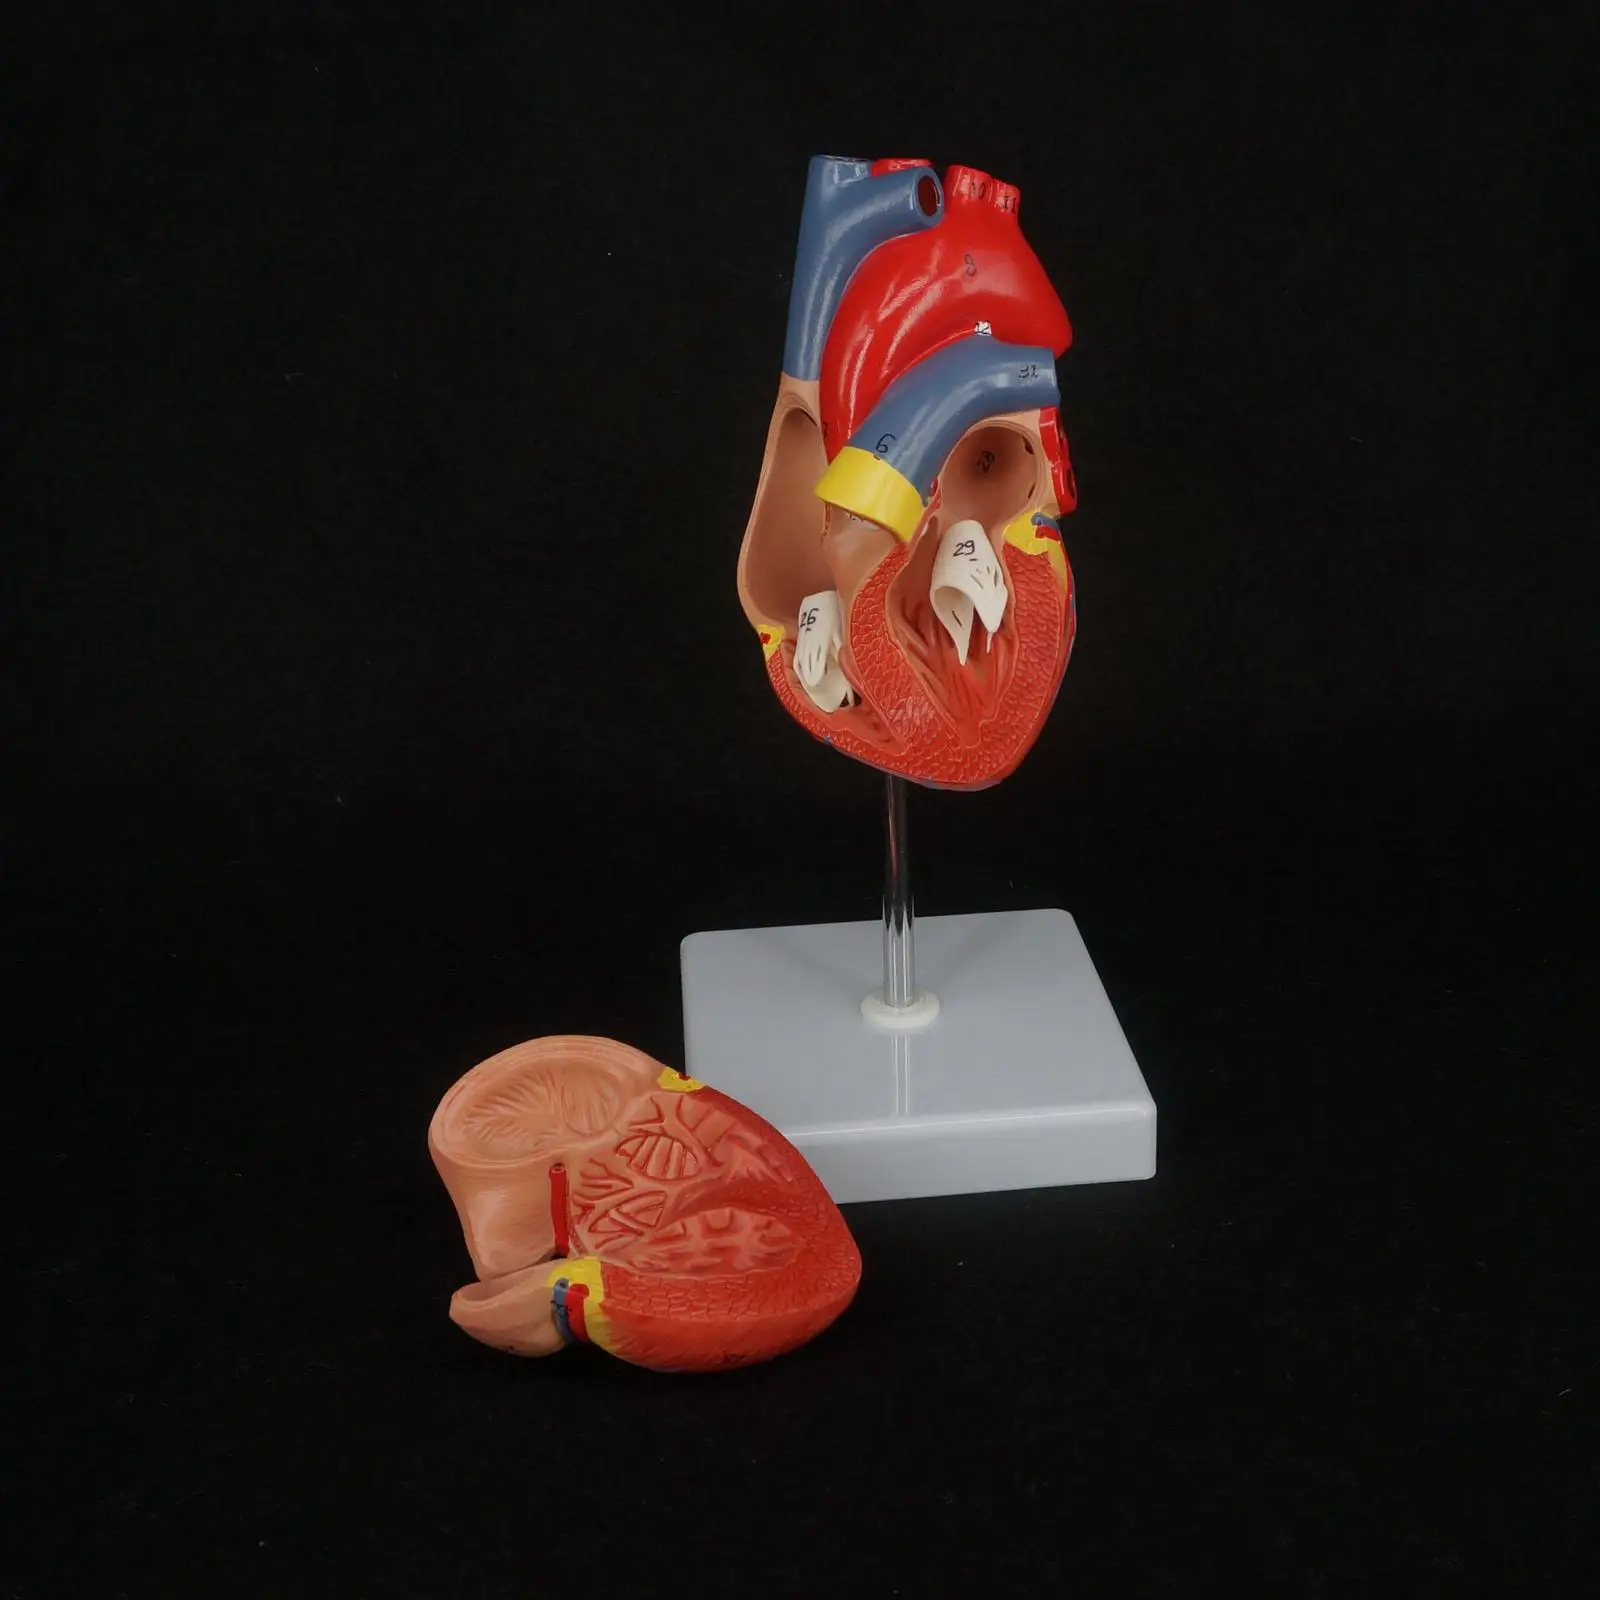

Фотографии и 3D-модели анатомии сердца человека